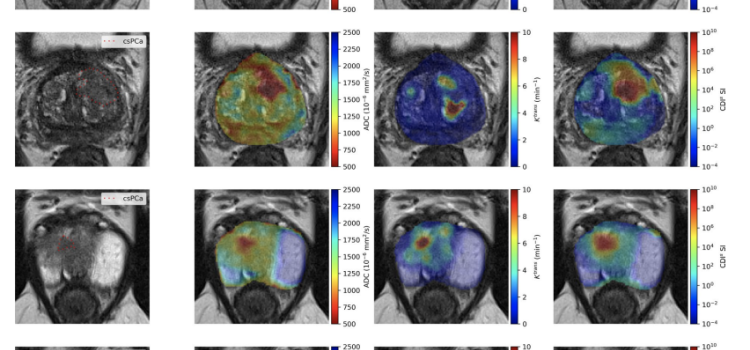

News and new technology innovations concerning how imaging technology for the lungs. This includes computed tomography (CT), X-ray and ultrasound imaging of the lungs to diagnose and monitor treatment for lung cancer, COPD, pulmonary embolism (PE), pneumonia, tuberculosis and COVID-19 can be found on this channel.

April, 15, 2025 — Optellum has entered an agreement with Bristol Myers Squibb to leverage AI in early diagnosis and ...

July 3, 2024 — Results from a new study led by researchers at The University of Texas MD Anderson Cancer Center support ...

June 11, 2024 — A new study led by researchers at Emory AI.Health, published in the Journal of Computers in Medicine and ...